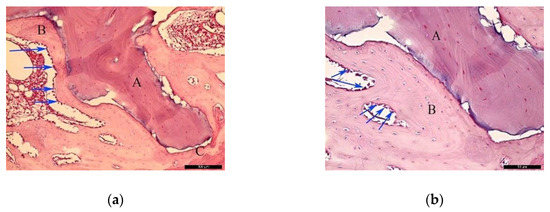

In the AG, after 30 healing days (Figure 3a), it was possible to observe the autogenous bone graft (A), and bone trabeculae under the receiving bed (B). The space between the graft and the recipient bed was occupied by bone tissue with a relevant number of trabeculae in the maturation stage with high cellular activity and good vascularization (C). Focusing on the graft (Figure 3b), autogenous bone (A) and newly formed bone (B) could be identified. In the inner part of the autogenous bone graft, small areas of resorption (black arrows) might indicate a phase of remodeling.

Figure 3.

Histological analysis of the autogenous group (AG) at 30 days. (a) Autogenous bone graft (A) positioned over the recipient bed (B), trabeculae in maturation stage and good vascularization (C); space previously occupied by the osteosynthesis screw is recognizable in (D). Hematoxylin and eosin stain at a magnification 40×; (b) Autogenous bone (A) newly formed bone (B), and small areas of resorption (black arrows). Hematoxylin and eosin stain at a magnification 125×.

In the AG, after 60 post-operative days (Figure 4a), it was possible to observe the autogenous bone graft (A) in contact with the newly formed bone (B). Internally, the presence of connective tissue areas might suggest a remodeling phase of the bone. The identification of anucleated cells could suggest the presence of osteoblasts (red arrows). At the microscopic examination (Figure 4b), it was possible to distinguish the autogenous bone graft (A) and newly formed bone (B) separated by a cement line (black arrow). In the inner part of the autogenous bone graft, connective tissue areas were noticed, confirming the remodeling phase of the bone. Osteocytes were clearly visible (red arrows).

Figure 4.

Histological analysis of the AG at 60 days. (a) Autogenous bone graft (A) in contact with the newly formed bone (B), and anucleated cells suggesting the presence of osteoblasts (red arrows). Hematoxylin and eosin stain at a magnification 40×; (b) Autogenous bone graft (A) and newly formed bone (B) separated by a cement line (black arrow) and osteocytes (red arrows). Hematoxylin and eosin stain at a magnification 125×.